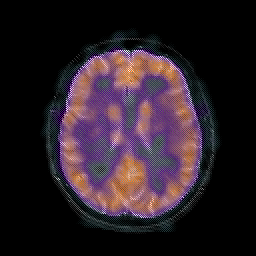

AIDS dementia: overlay -- Slice #11

[Home][Help][Clinical][Tour 1] Slice 11